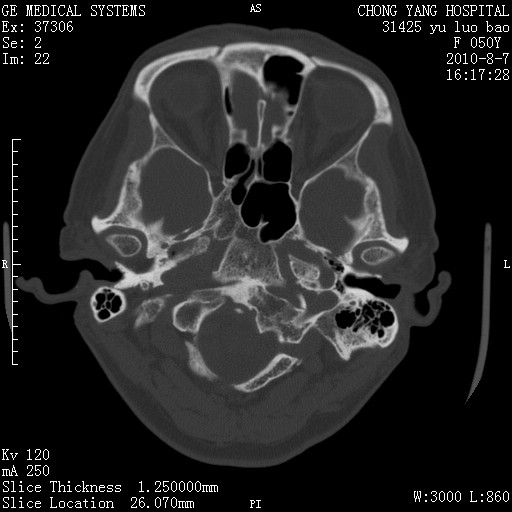

标题: CT28285:听力下降一年,头昏。 [打印本页]

标题: CT28285:听力下降一年,头昏。

骨窗示右侧内听道扩大,考虑右侧听神经瘤。

右侧桥小脑角去等密度占位,右侧内听道扩大、骨质吸收,考虑:右侧听神经瘤,建议增强检查。